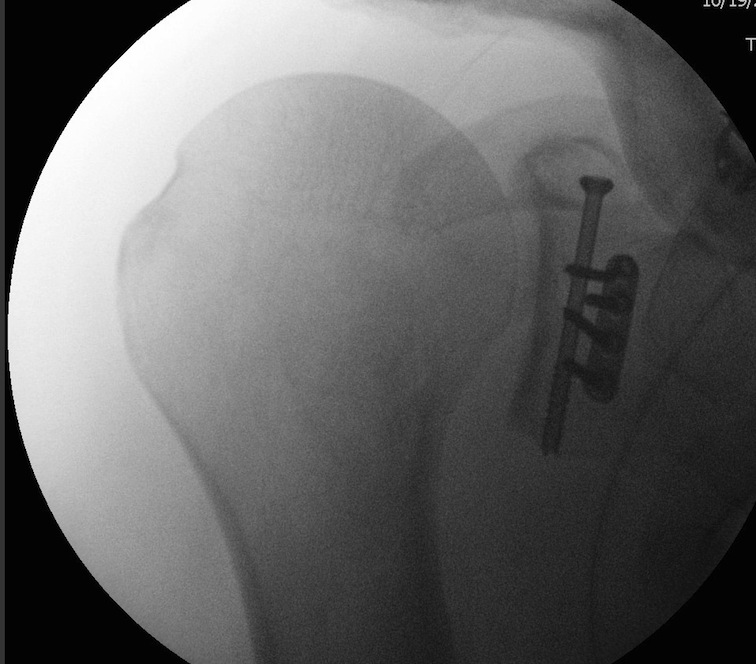

Case 1

- > 1 cm medial displacement

- ORIF via posterior / modified Judet approach

Case 2

Combined Glenoid and Scapula Fractures

Case 1

- displaced glenoid fracture and neck fracture

- ORIF both through posterior / Judet approach